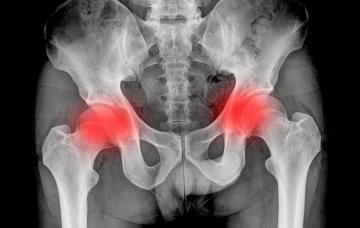

Espondilitis anquilosante

Los síntomas de esta afección varían mucho de una persona a otra, y al principio la exploración física es normal y los dolores son moderados, por lo que el diagnóstico de espondilitis anquilosante se puede retrasar entre uno y tres años.